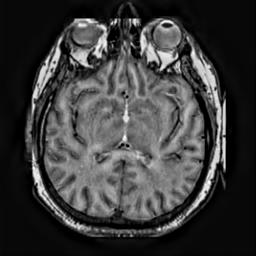

To demonstrate the effectiveness and efficiency of the proposed image fusion method , we conduct a set of comparative experiments on three image datasets. The first is composed by 8 pairs of multi-modal medical images and the second one contains 15 pairs of multi-focus gray or color natural images. These two datasets are often used in many related papers and some examples are shown in Figure 3(a) and Figure 3(b). The third one is a new multi-focus cervical cell image dataset collected by ourselves, which consists of 15 groups of color images and each group contains a series of multi-focus cervix cell images with size of or , etc. Some source examples are shown in Figure 3(c). Our source code implemented in C++ along with the new multi-focus cervical cell image dataset is available online.

We first evaluate the performance of the proposed method under varying total number of octaves and number of layers sampled per octave. The fused images of a pair of multi-modal medical images with different and are shown in Figure 4. In this example, on the one hand, when only 1 or 2 octaves are involved in constructing the DoG pyramid, the fused images fail to keep the integrity information of large size objects (e.g. eyeballs), while by increasing the value of , the integrity information of eyeballs is preserved. On the other hand, although not as significant as the increase of octave numbers , the fused image can contain more details by the increase of layer numbers . The corresponding objective quality metrics are shown in Figure 5. As shown in Figure 5(a), most of the metric values are improved as the number of octaves increases with the fixed layer numbers 3 in the global tendency and each of them tends to be stable when the number of octaves is 5. To get a relatively good quality from Figure 5(b), we can notice that some of the metric values can get a good performance when the number of layers is 3, such as the MI, SSIM, QI and VIF, though there are only a little change of all the metric values by increasing the number of layers with the fixed octave numbers 5. Because it will result in more computation burden with the increase of the value and , and for different kinds of source images, there are different performance with the diverse parameter settings. To get a trade-off between them in our experiments, we set for the multi-modal dataset, for the natural datasets and for the multi-focus cell dataset, respectively.

Figure 6 shows the fused images obtained by different methods with the multi-modal source images shown in Figure 3(a). As shown in these figures, the proposed method can produce images which preserve the complementary information of different source images well. Moreover, due to the scale-invariant structure saliency selection, our method can keep the integrity information of large size objects and the visual details simultaneously. Although the fused image generated by other methods can also capture the details to some extent, all of them fail to keep the integrity information of large size objects such as the eyeballs. Furthermore, from Figure 6(k)-6(t), the DTCWT, GFF, IM and NSCT methods may decrease the brightness and contrast while the proposed method can preserve these features and details without producing visible artifacts and brightness distortions.